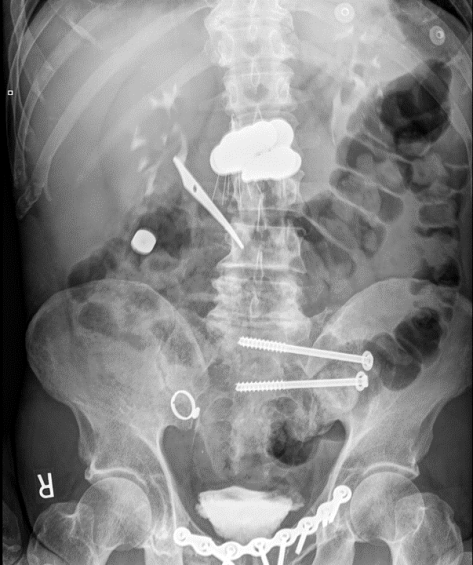

A 37yo F with history of anxiety presented with nausea and palpitations after ingesting 160 pills of Diurex in an attempt to fix her constipation for the past 2 weeks. Prior to arrival to the hospital, the paramedics administered activated charcoal. She was tachycardic, mildly hypotensive, hypokalemic, and acidotic (AG 20). Methamphetamine was found in her system as well. Fortunately she improved with fluids and supportive measures, but lethal cases of caffeine overdose, while rare, have been described in the medical literature!